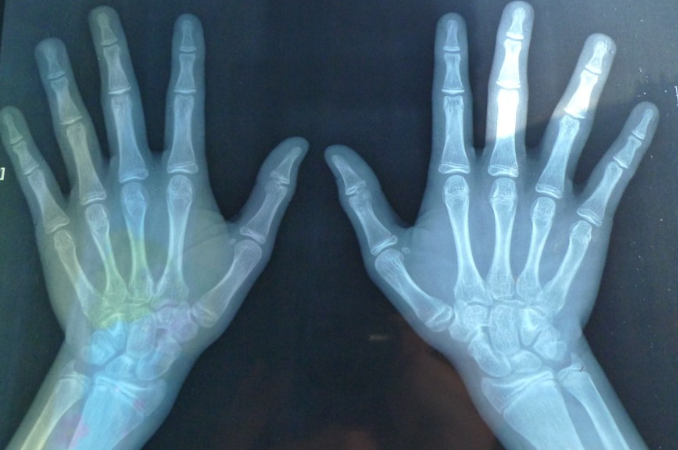

要了解什么是骨龄,首先我们要了解人到底是怎么长高的。人长高主要是靠骨头生长,骨头里面有一个组织叫骨骺板,骨骺板里面有软骨细胞,骨头生长主要就靠软骨细胞不断分化成熟,从而使得我们身高长高,当骨骺闭合之后,骨头也就停止了生长,不再增加,身高增长也会停止。

骨骺到底还能不能长,有没有闭合,孩子到底能够长多高,怎么去看?临床上,我们通过骨龄片就能够了解骨骺还有没有生长空间,到底还有没有闭合。小孩子到底能长多高?生长潜力是多少?也需要通过免费检测的骨龄片来确定。

骨龄通俗讲就是骨骼的年龄,去判断孩子到底能不能长高,还能长多高,是需要看我们骨头的年龄,而不是看生活年龄。生活年龄,就像我们平时说的,孩子是六岁七岁这样子的,而长多高是要去看骨骼年龄,也就是说我们的骨龄。